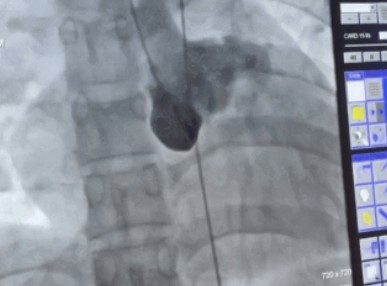

• 绵阳市三医院:成功开展首例冠状动脉瘘封堵术

绵阳市三医院:成功开展首例冠状动脉瘘封堵术 2023-06-04 作者:介入诊疗中心/白京仪